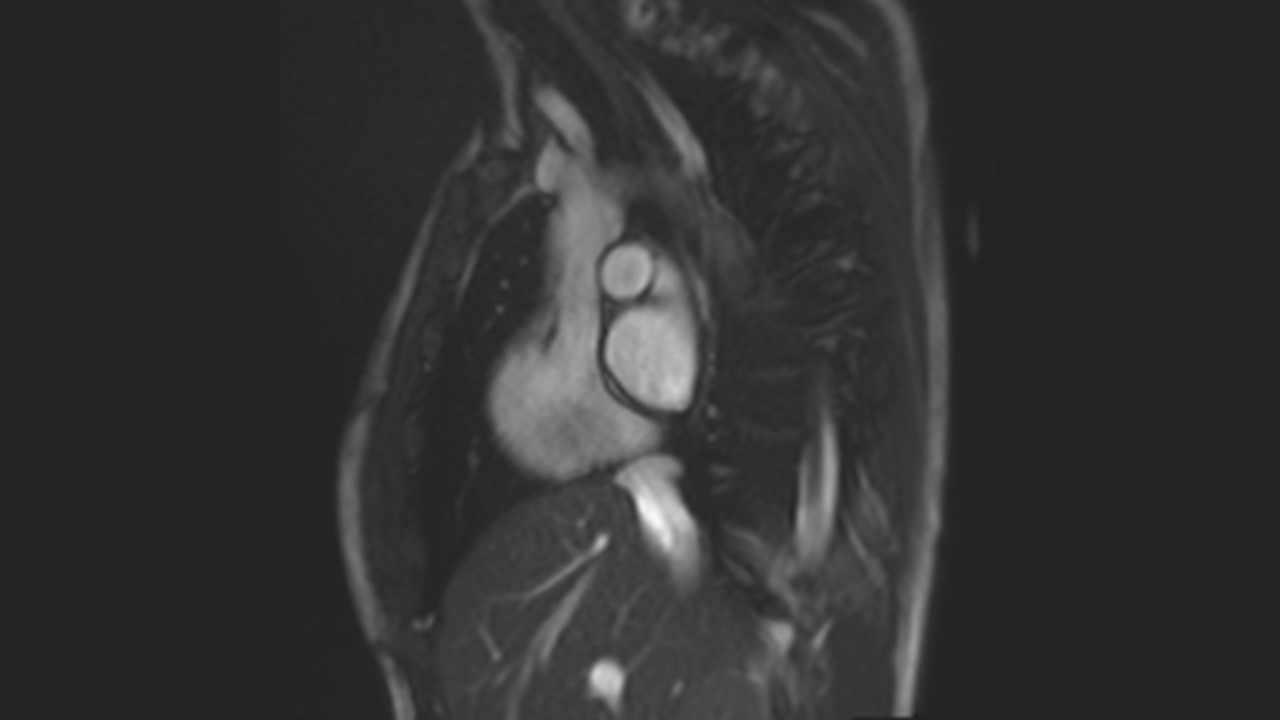

Aortic Root Series

Aortic Arch Series